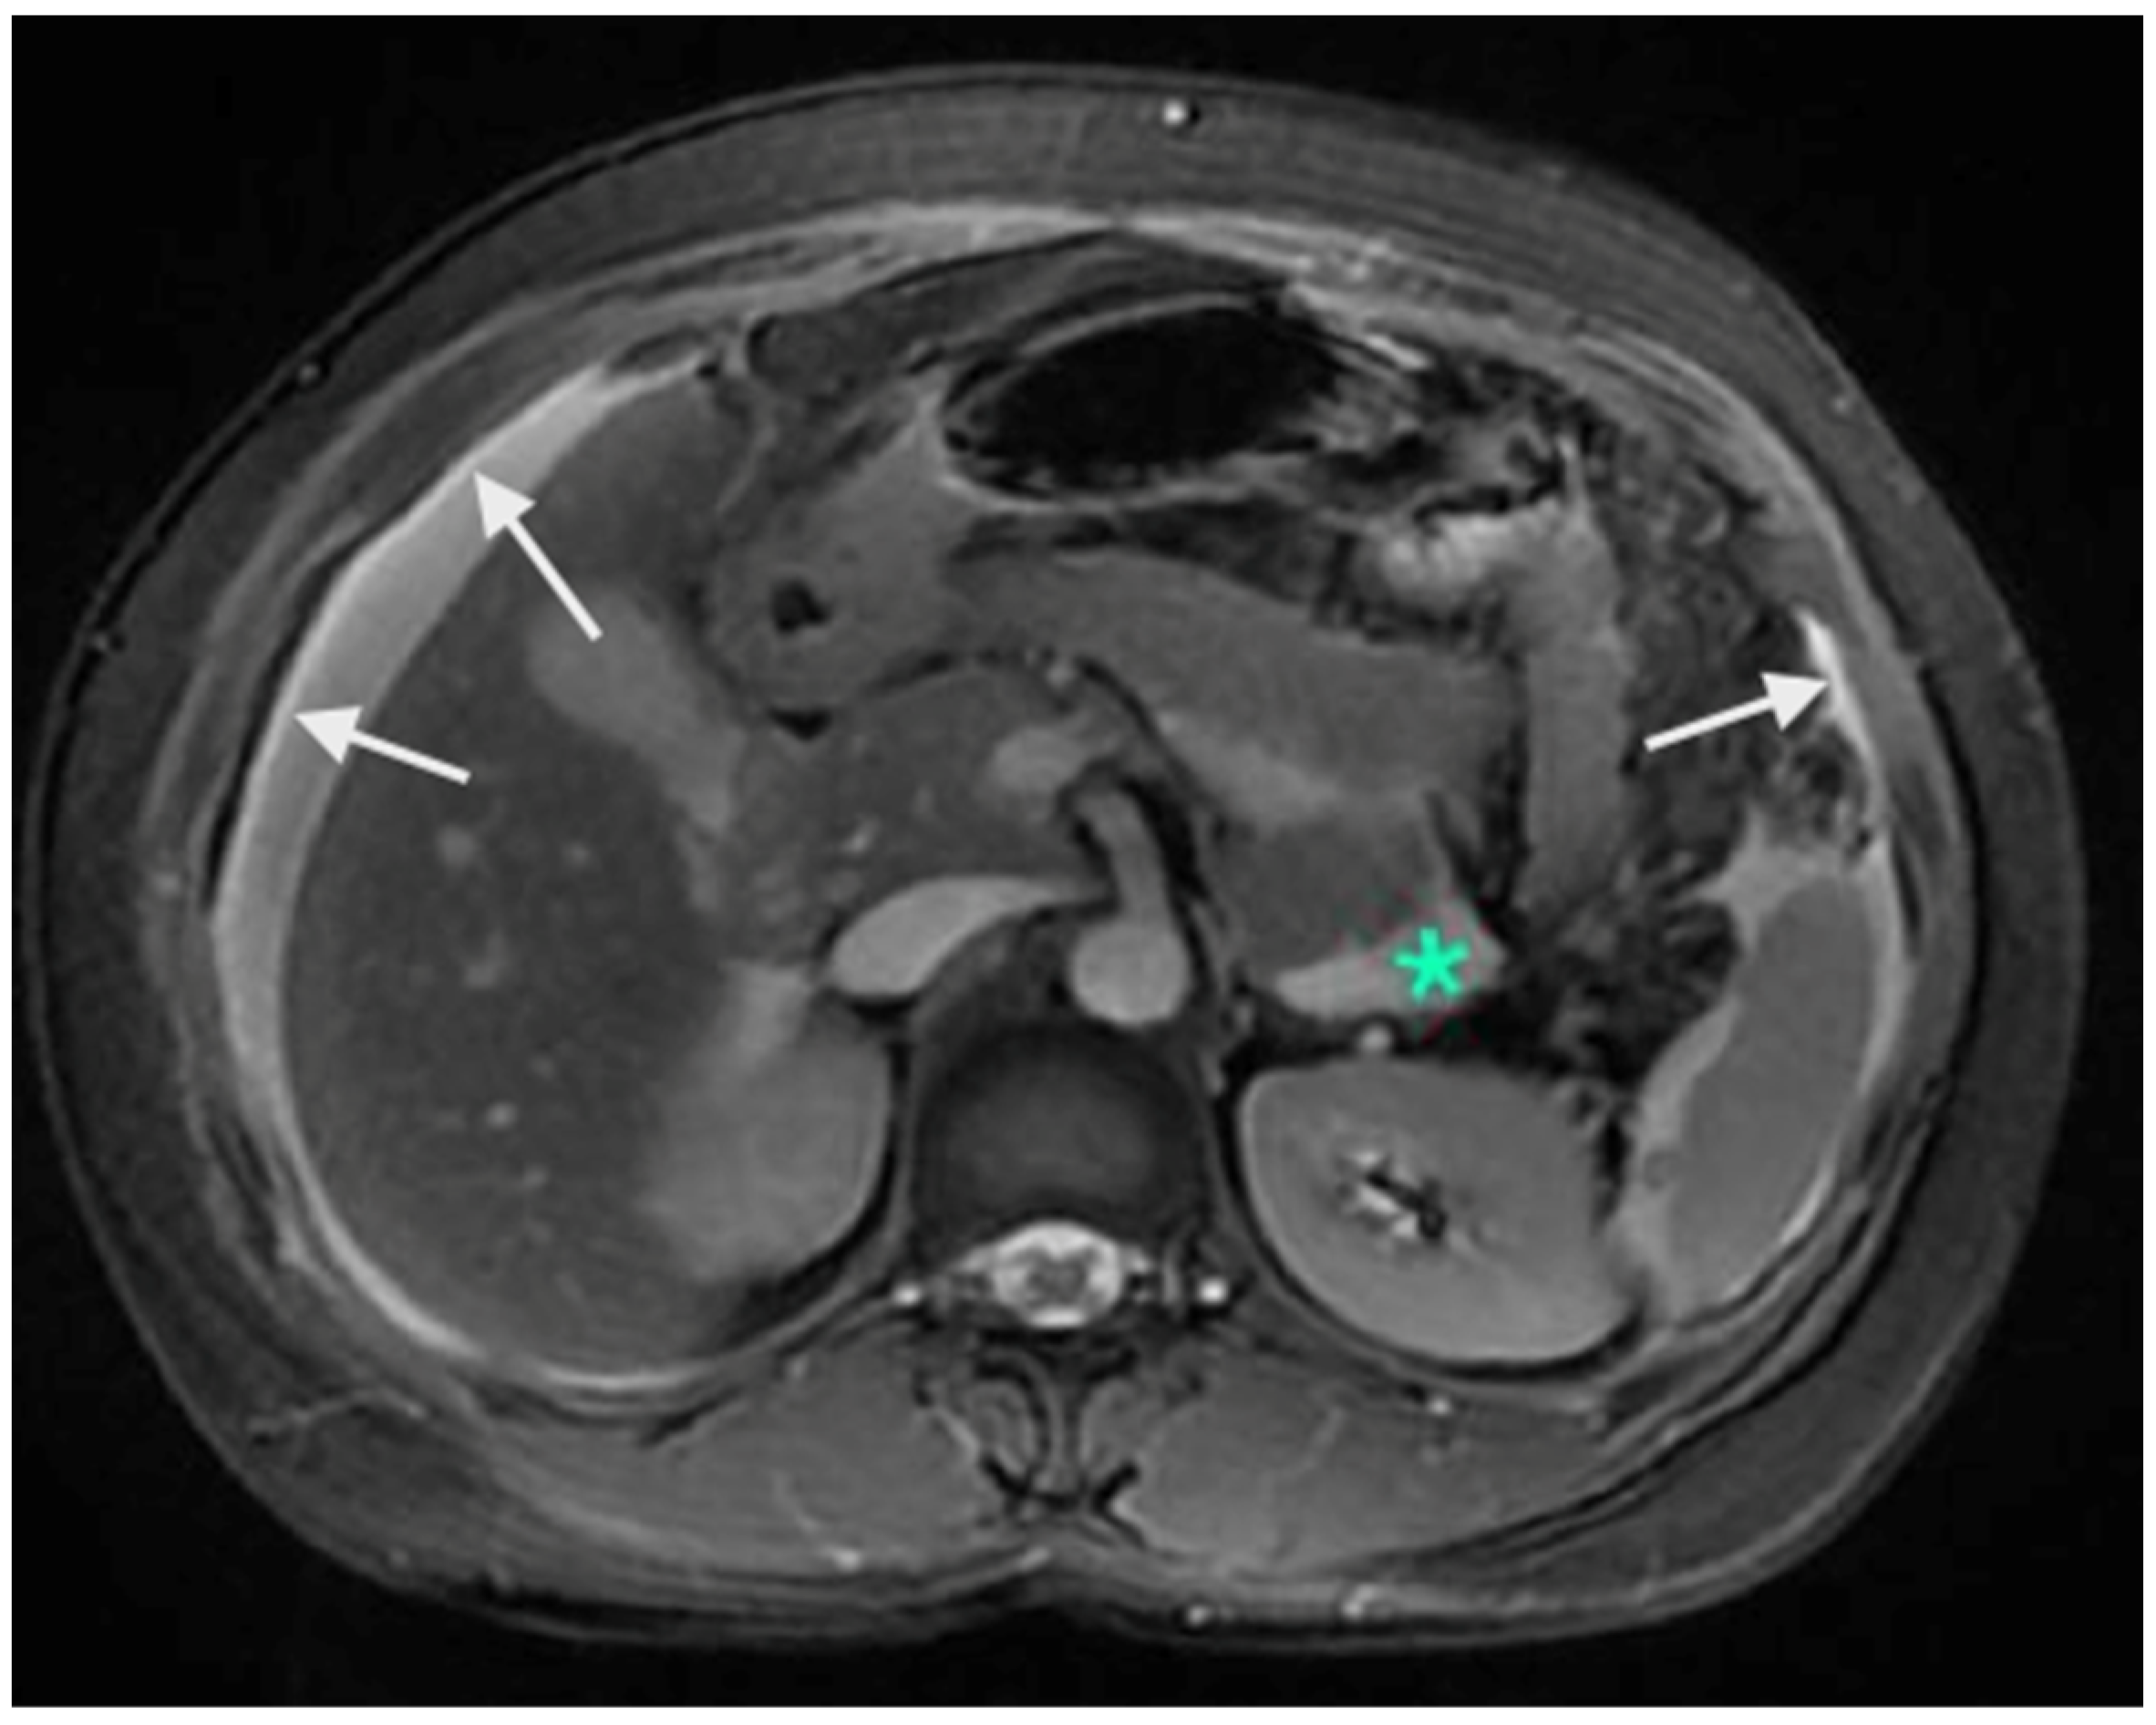

There are no studies evaluating the performance in the upper abdomen, but subtle peritoneal thickening and nodularity are more accurately detected on MRI compared to a CT scan (Figure 3) [53]. The regional lymph node stations described above should be studied on imaging to identify the nodal disease (Figure 4). Considering disease in the upper abdomen alone, extensive disease in the gastrocolic ligament infiltrating the head of the pancreas, extensive infiltration of the stomach, disease infiltrating the porta hepatis, and diffuse and massive involvement of the subphrenic region are pointers of extensive disease that is not amenable to a complete cytoreduction. No one finding can be considered in isolation, and it is the overall disease extent and the general condition of the patient that are considered while deciding to proceed with CRS or not. Though many surgeons perform a staging laparoscopy to select patients for CRS, these obvious signs of inoperability on imaging could avoid an unnecessary surgical procedure [54].

Figure 3.

Contrast-enhanced MRI showing A: enhancement of the peritoneum (white arrows). These changes are picked up earlier on MRI compared to a CT scan. The green * shows a fluid collection without any nodularity or thickening and is not scored as a peritoneal deposit.